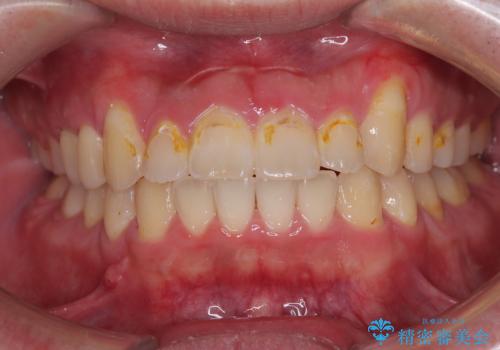

【ワイヤー矯正】八重歯 歯のでこぼこを治したい!

下顎前歯の叢生を短期間で改善

担当医 河口智英